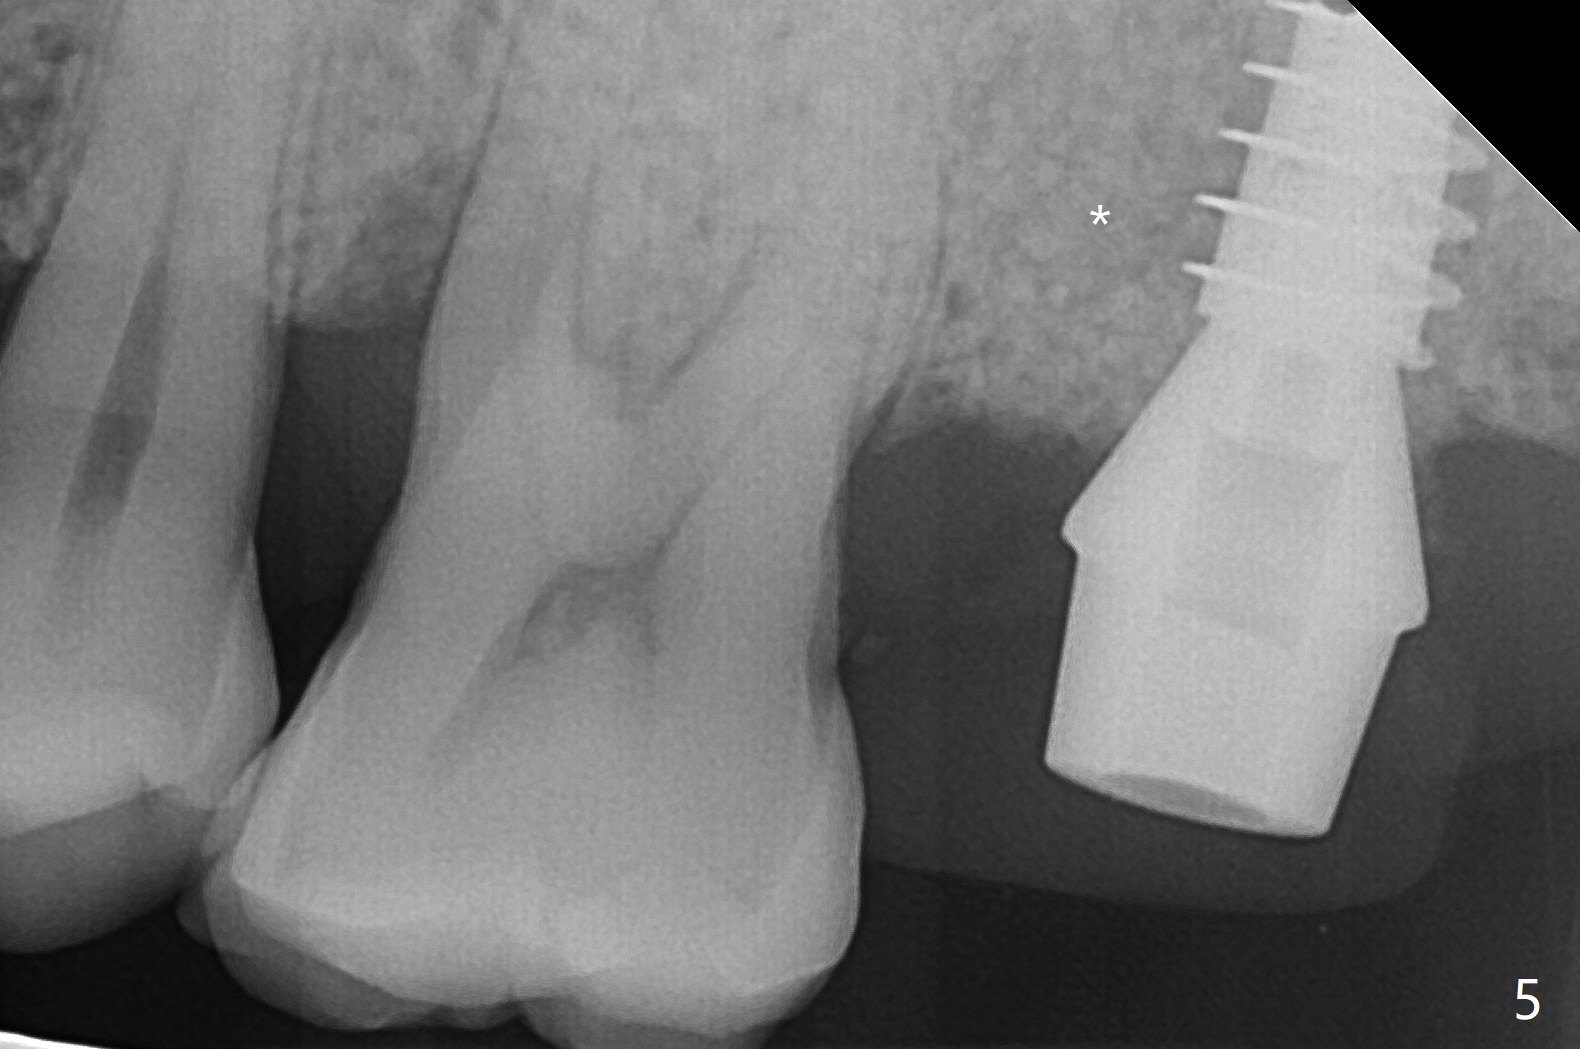

尽管腭侧(P)根周围骨质吸收严重(图三(术前设计)),15号牙拔除还挺困难,因为两个颊侧根骨质吸收不明显,而腭侧根表面许多结石(说明牙周病变)。导板使用中,金属圈脱落,插回后还能用(图一(术后拍摄)),完成种植(图二)。金属圈脱落可能是因为近中塑料太少了(图一,二:箭头)。植体(图四:绿色)和基台(粉红色)放置后,粘性骨粉植骨(红圆圈)前,在腭侧缺失处塞入一块胶原塞(浅蓝色),最后缺损充填完善(图二,五比较(*))。